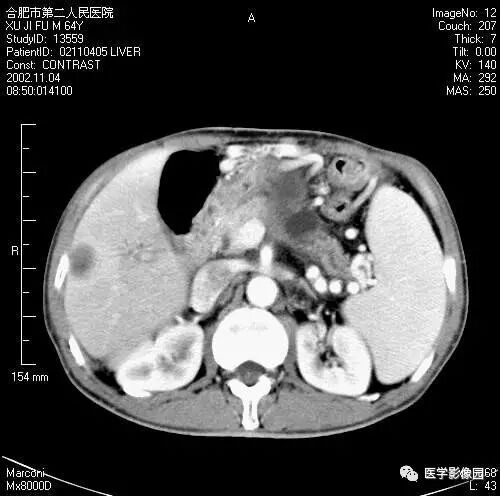

图6-4-16胰腺癌

A. 增强扫描见胆总管扩张(↑),

胆囊扩大,左肾有两个小囊肿;

B.(与A图间隔5mm的层面)扩张的总胆管

突然中断、消失,钩突部见低密度肿块